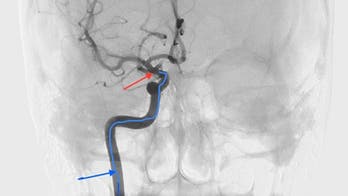

Stroke October 28, 2015 Stem cells can be safely infused in brain to promote stroke recovery, study finds A yearlong study of stroke patients has found that stem cells from a patient’s bone marrow can be safely infused in the brain through the carotid artery to promote recovery. Researchers at the Interdisciplinary Stem Cell Institute at the University of Miami Miller School of Medicine followed 48 patients, more than half of whom who were treated using stem cells, and found recovery along with no adverse side effects when compared with their counterparts.